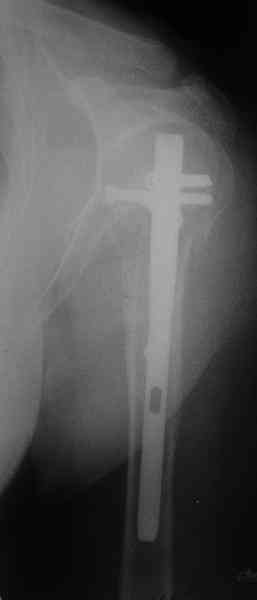

We don’t see the nonunion in this part of humerus to often. If hi has now not very bad rate of motion in the joint, may by you can try a conservative treatment with the traction cast bandge for the first time (1-2 weeks), and then the intensive physiotherapy. For the operative treatment I would like to take the Proximal Humeral Nail if it is possible (not an intraarticular fracture). This implant is by my opinion less invasive.

Best regards, Ivan Sirotin.

Another option could be closed nailing, see an example, the surgery was done 2 days ago. In common such surgeries are performed under regional anesthesia, not general.

One more option can be fixation by V-shape stressed wires.